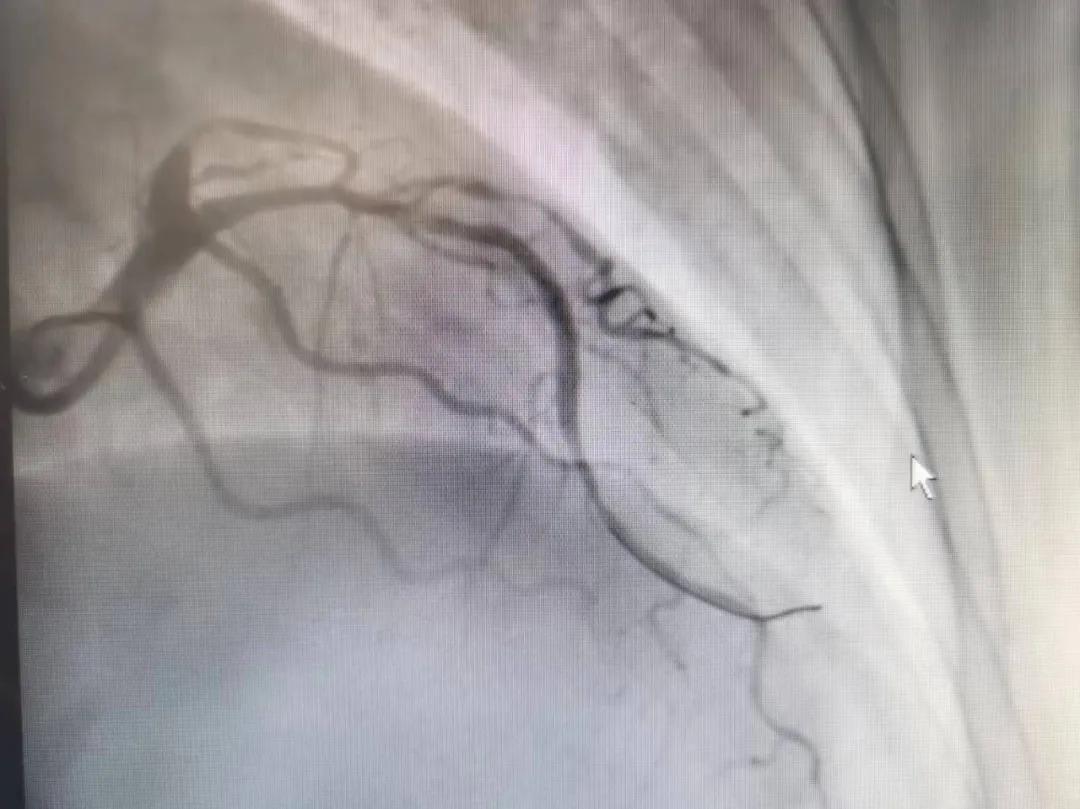

病人是位六十多歲的女性患者,有長期高血壓病史,1個月前開始出現(xiàn)胸悶胸痛,口服藥物治療效果不佳,經(jīng)朋友介紹,來到市二院心血管內(nèi)科。入院后完善冠狀動脈造影提示:前降支全程彌漫性狹窄伴鈣化,最重95%,回旋支狹窄約85%,右冠脈全程狹窄伴鈣化,最重60%。血管內(nèi)超聲顯示右冠脈開口面積3.36mm²,可見環(huán)形鈣化,考慮患者病變程度重、鈣化明顯,常規(guī)器械無法實現(xiàn)病變的良好預(yù)處理,且有很高的冠脈穿孔、血管夾層的風(fēng)險。

術(shù)前

王瑾院長和李慧新主任帶領(lǐng)介入團隊充分評估,決定行前降支冠狀動脈鈣化病變旋磨術(shù),術(shù)中應(yīng)用1.5mm旋磨頭,以15萬-17萬轉(zhuǎn)/分速度共對病變旋磨3次,累計旋磨時間60秒,后復(fù)查造影示鈣化明顯減輕,為后續(xù)操作創(chuàng)造了良好條件,隨后應(yīng)用預(yù)擴張球囊、切割球囊再次處理病變,并順利植入支架1枚,復(fù)查造影顯示支架膨脹及貼壁良好,無夾層、血腫、慢血流等情況,手術(shù)順利完成。患者術(shù)后無不適,胸悶、胸痛癥狀明顯緩解,順利出院。